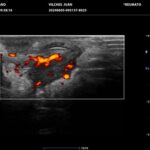

La HS es una enfermedad crónica, inflamatoria inmunomediada, sistémica, recurrente y debilitante de los folículos pilosos terminales con origen en las glándulas apocrinas de estos. Presenta habitualmente lesiones dolorosas, profundas e inflamadas, localizadas más frecuentemente en las regiones axilares, inguinales y anogenitales. El 80% de las lesiones tienen ubicación profunda de difícil acceso al examen físico. Su diagnóstico es clínico pero el ultrasonido (US) de alta resolución con Doppler es un método que cumple actualmente un rol esencial para establecer el diagnóstico, estadificar la enfermedad y detectar actividad, incluso en el caso de lesiones no pesquisadas en el examen físico. También nos permite monitorear el estado y la progresión de la HS, facilitando la evaluación rápida de distintos enfoques terapéuticos. Incluso, los cambios ecográficos pueden modificar la conducta terapéutica.

Los hallazgos ecográficos más relevantes son el ensanchamiento de folículos pilosos, engrosamiento y ecogenicidad anormal de la dermis, nódulos pseudoquísticos dérmicos, colecciones líquidas y tractos fistulosos. Por otro lado, el US nos permite valorar la localización exacta y extensión de las lesiones, su ecogenicidad, el grado de vascularización al examen Doppler y las eventuales complicaciones, e incluso la modificación de las lesiones en respuesta a la terapéutica instaurada. La HS se estadifica clínicamente mediante la clasificación de Hurley y los hallazgos ecográficos muestran correlación con cada estadio clínico.

El diagnóstico ecográfico resulta de importancia diagnóstica, tal es así que la ecografía de alta resolución y el estudio Doppler han ocupado un lugar preponderante en los últimos años. La ecografía de la piel permite identificar lesiones no encontradas en el examen físico, evaluando de manera fehaciente su extensión anatómica. El empleo de la ecografía en la HS es ideal, ya que el 80% de las lesiones ocurren en las capas más profundas y no en la superficie de la piel. Permite evaluar la localización exacta y extensión de las lesiones, su ecogenicidad, el grado de vascularización al examen Doppler, las eventuales complicaciones, e incluso la respuesta terapéutica.

El estudio ecográfico de alta resolución con Doppler tiene un rol fundamental en la categorización de las lesiones de HS en profundidad, incluso las subclínicas. Debemos incluir al US como técnica de elección para estadificar y monitorear pacientes con HS, ya que nos permite acceder a un diagnóstico rápido de lesiones típicas con las que podremos, en conjunto con la clínica, estadificar y seguir en el tiempo a los pacientes.